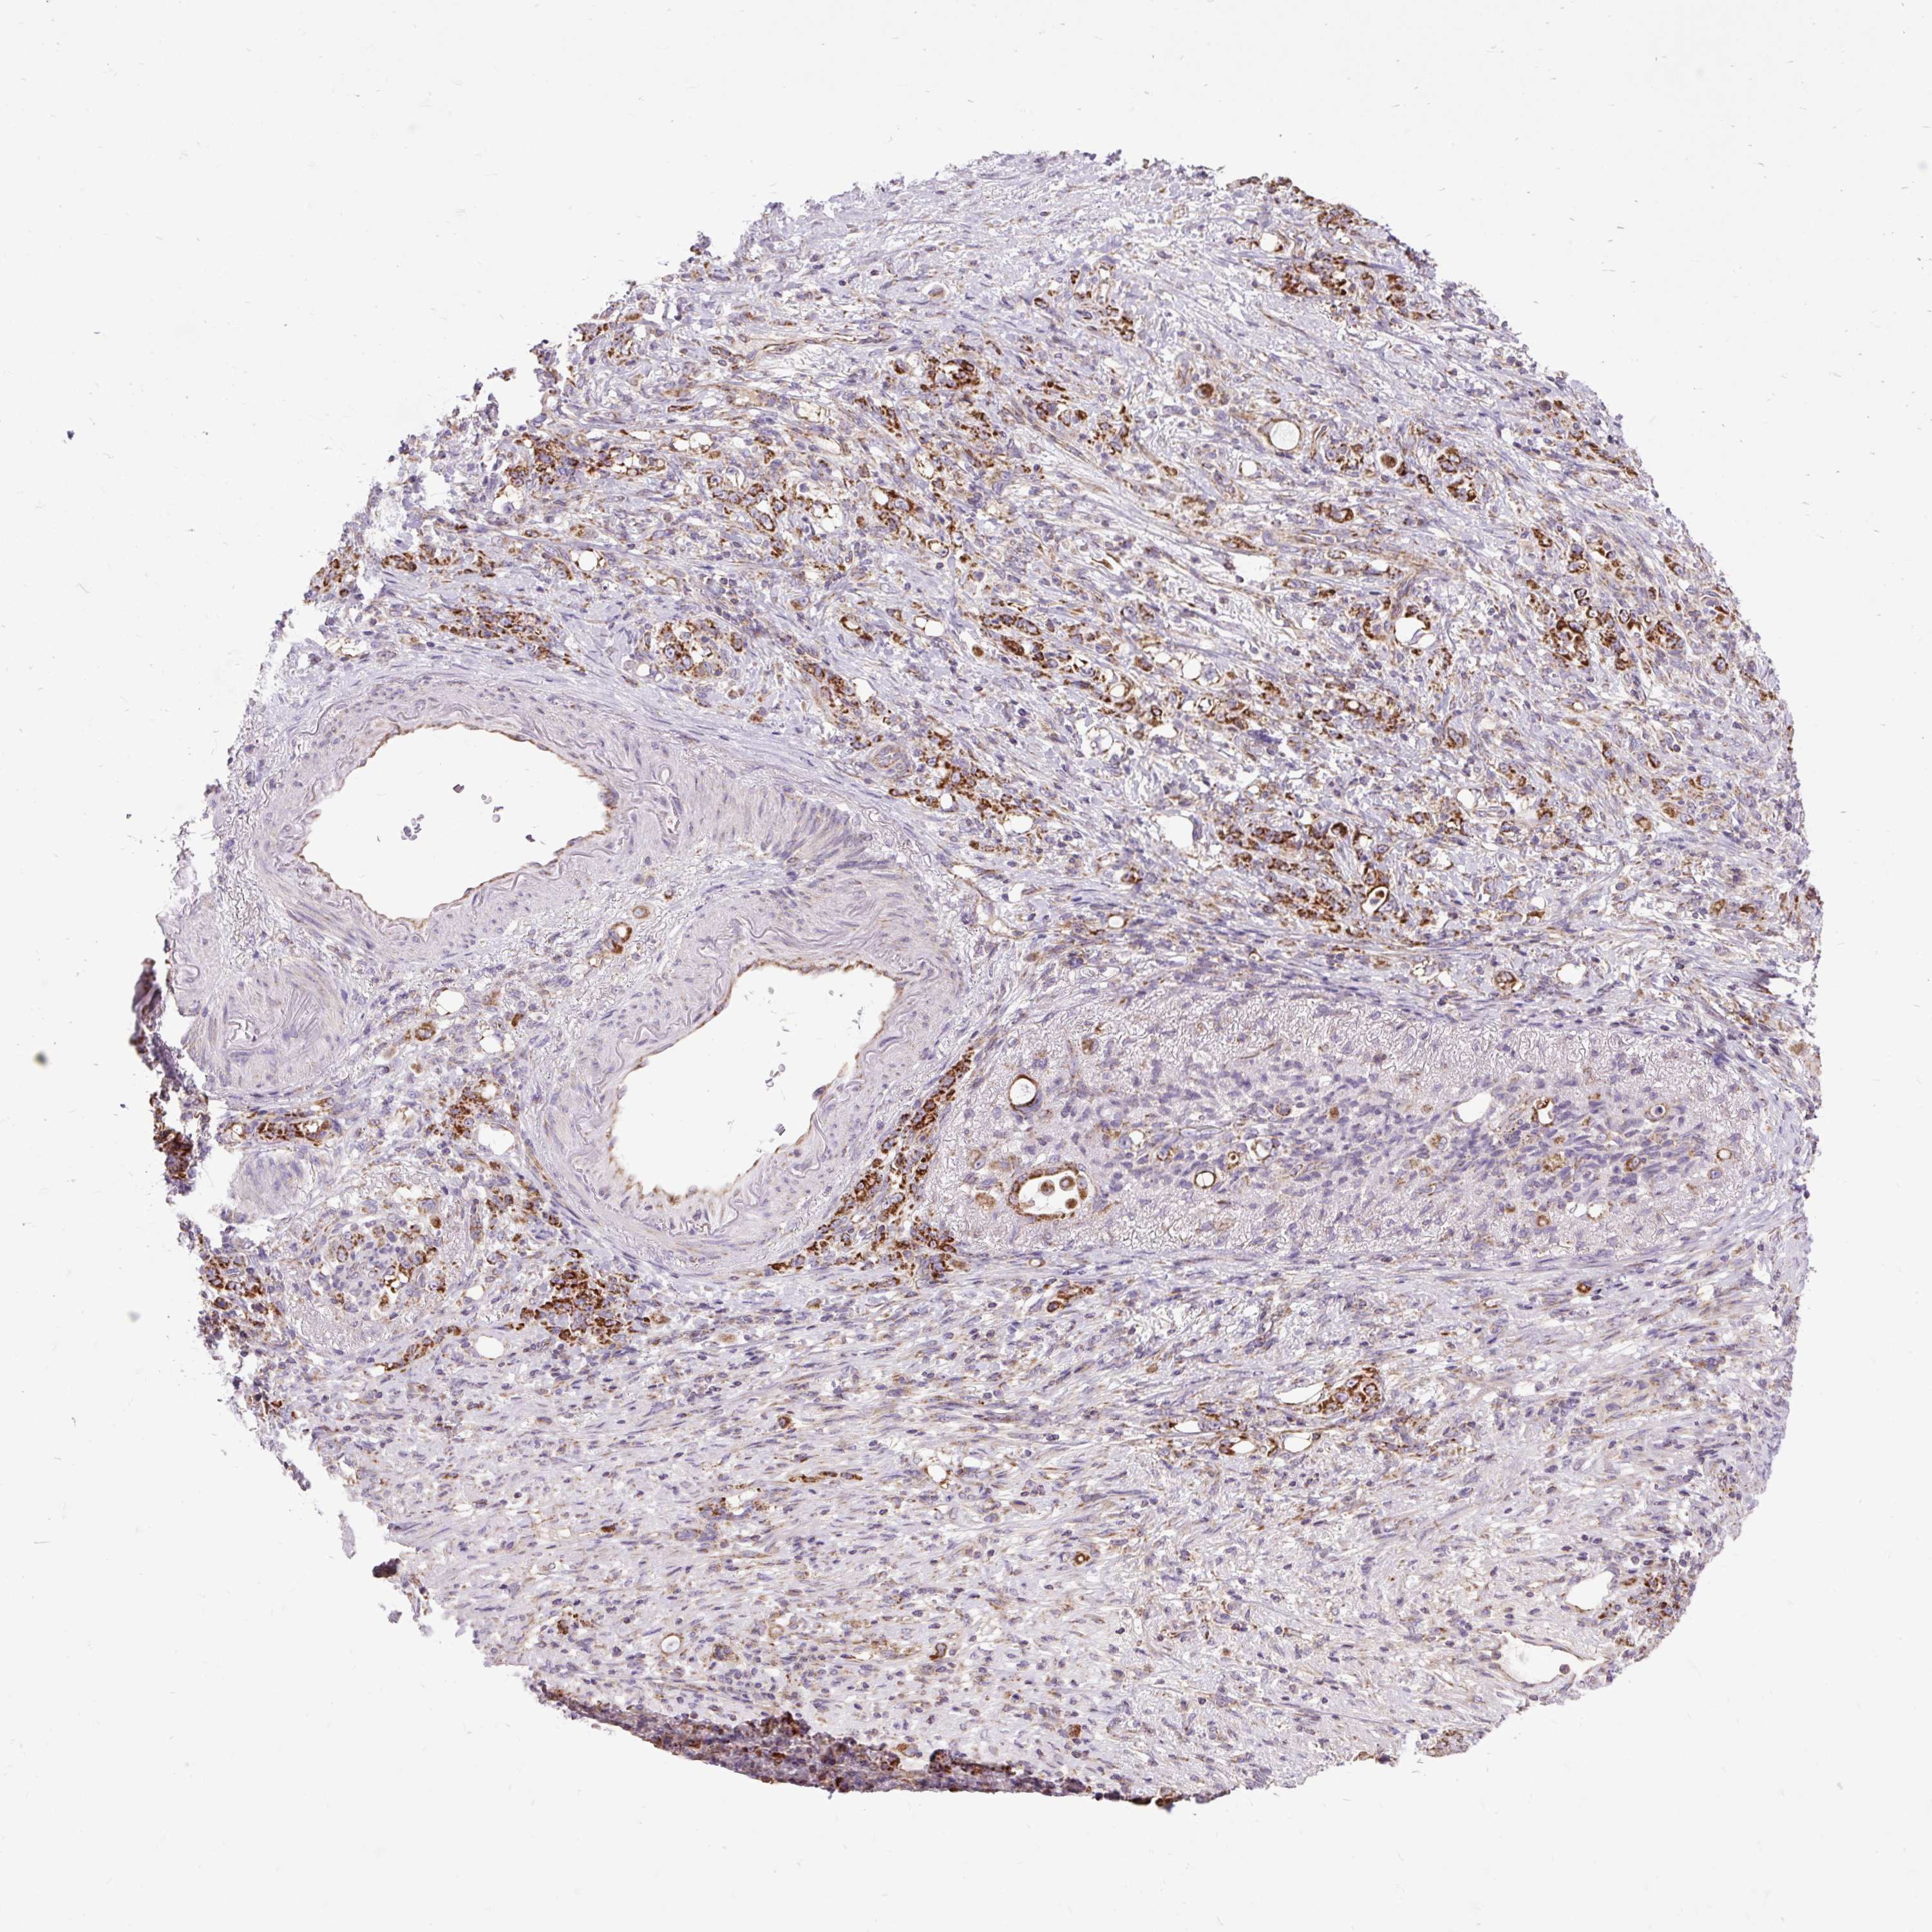

STOMACH CANCER - Protein expressioni

A mouse-over function shows sample information and annotation data. Click on an image to view it in a full screen mode. Samples can be filtered based on level of antibody staining by selecting one or several of the following categories: high, medium, low and not detected. The assay and annotation is described here.

Note that samples used for immunohistochemistry by the Human Protein Atlas do not correspond to samples in the TCGA dataset.

Antibody stainingi

Antibody staining in the annotated cell types in the current human tissue is reported as not detected, low, medium, or high, based on conventional immunohistochemistry profiling in selected tissues. This score is based on the combination of the staining intensity and fraction of stained cells.

Each image is clickable and will lead to virtual microscopy that enables deeper exploration of all samples and also displays staining intensity scores, fraction scores and subcellular localization as well as patient and tissue information for each sample.

Antibody HPA036231

Antibody HPA036232

Staining

High

Medium

Low

Not detected

Intensity

Strong

Moderate

Weak

Negative

Quantity

>75%

75%-25%

<25%

None

Location

Nuclear

Cytoplasmic/membranous

Cytoplasmic/membranous,nuclear

Adenocarcinoma, NOS